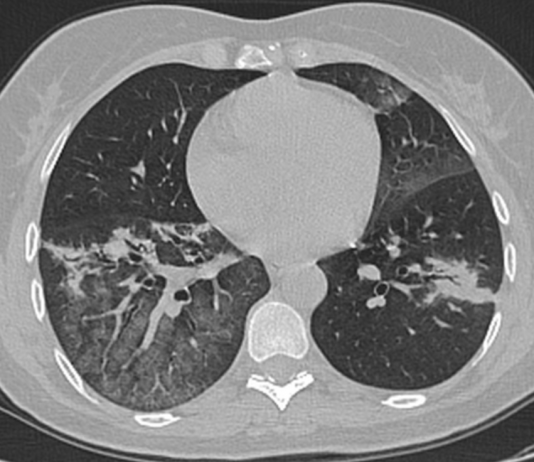

Paziente uomo, 38 anni, trasportato dal 118 con febbre e tosse da 5 giorni, trattato con zitromax e tachipirina senza...